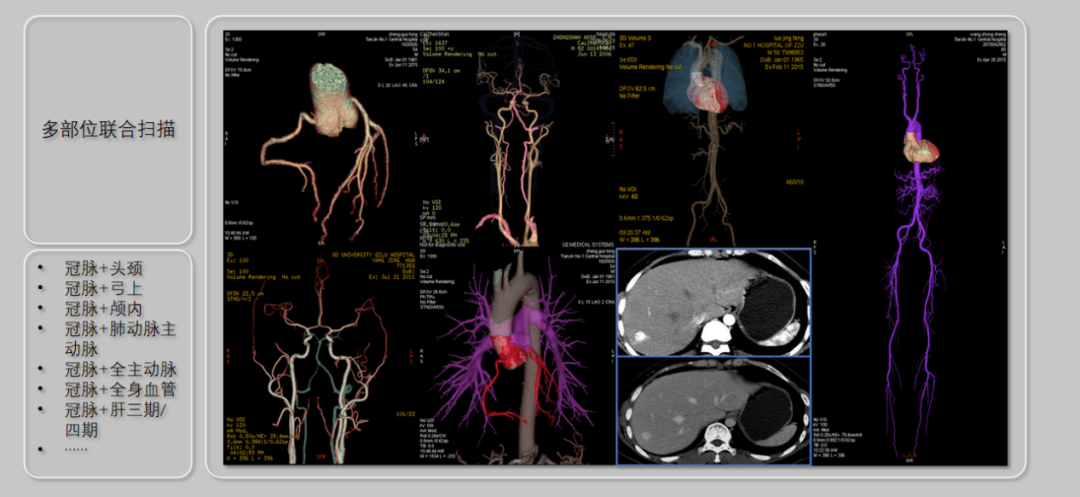

全身血管成像:一站式自由组合

针对多部位扫描需求,其独有的自由组合一站式联合扫描技术,实现扫描模式快速切换。患者一次造影剂注射,即可完成全身多部位血管(涵盖头颈、下肢等)联合成像,替代传统多次预约扫描,为临床一次性解决复杂问题,打破检查禁忌,提升诊疗效率 。